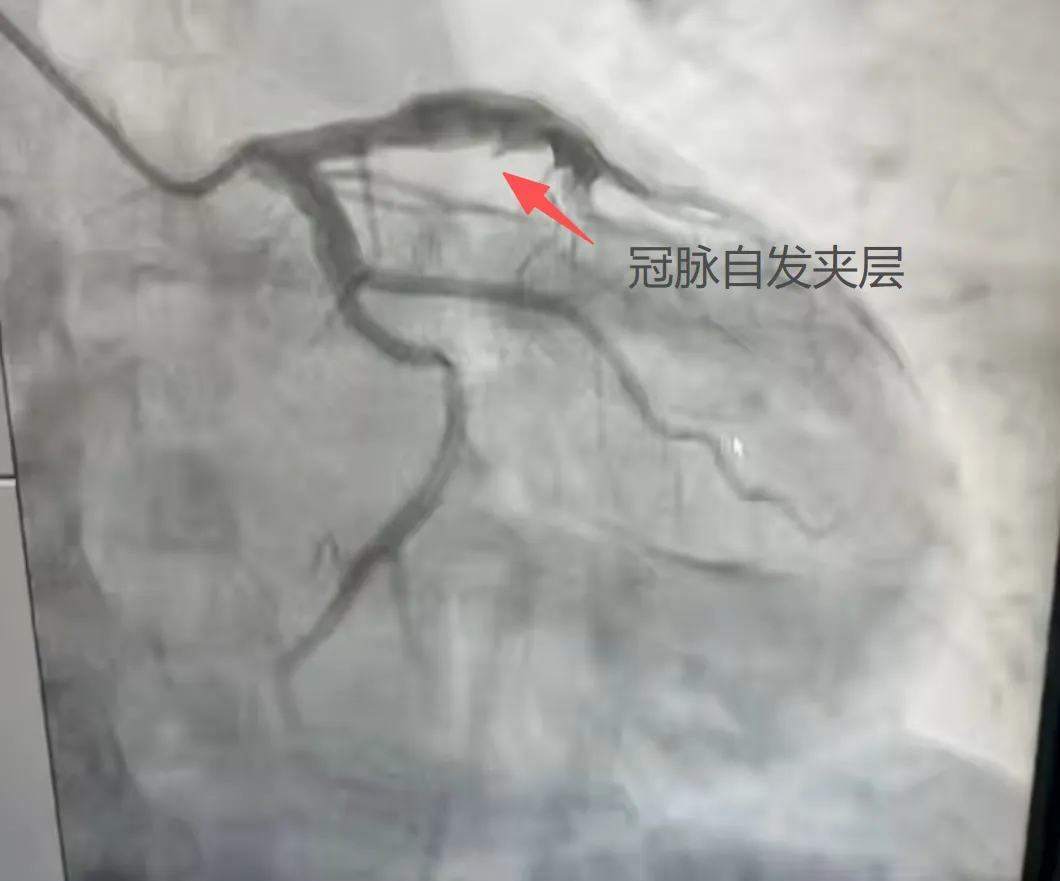

很快,姜先生被医护人员推入了急诊介入室。心血管科副主任医师张竹华、主治医师张振民迅速为姜先生完善了冠状动脉造影检查。结果提示姜先生左前降支近段管腔异常粗大,并伴有自发夹层形成;为充分评估血管情况,通过冠状动脉血管内超声(IVUS)检查,确认了姜先生本次心肌梗死就是因为冠脉自发夹层导致的,且左前降支近段异常粗大,最大直径已超过8mm。

from clipboard冠脉造影提示左前降支近段管腔粗大伴自发夹层